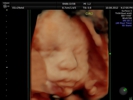

Fotografías de ecografías 4D HD/5D

Haga click sobre las imágenes para ampliar